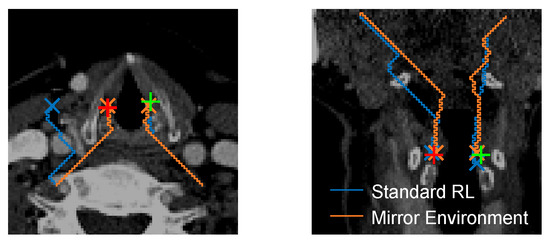

Mirror Environment

| LVF | Left vocal fold |

| RVF | Right vocal fold |

| RL | Reinforcement learning |